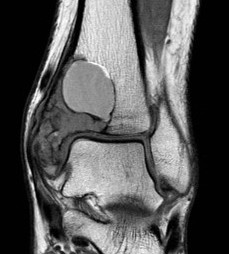

MRI

Usually difficult to determine UBC from ABC

- cystic lesions

- haemosiderin content - low to intermediate signal on T1 and T2

- borders and septae enhance with contrast

Fluid - Fluid levels

- due to sedimentation of RBC's & serum within the cavities

- patient must remain motionless for 10 minutes prior to the scan being performed

- allows time for sedimentation

- can also be seen in UBC